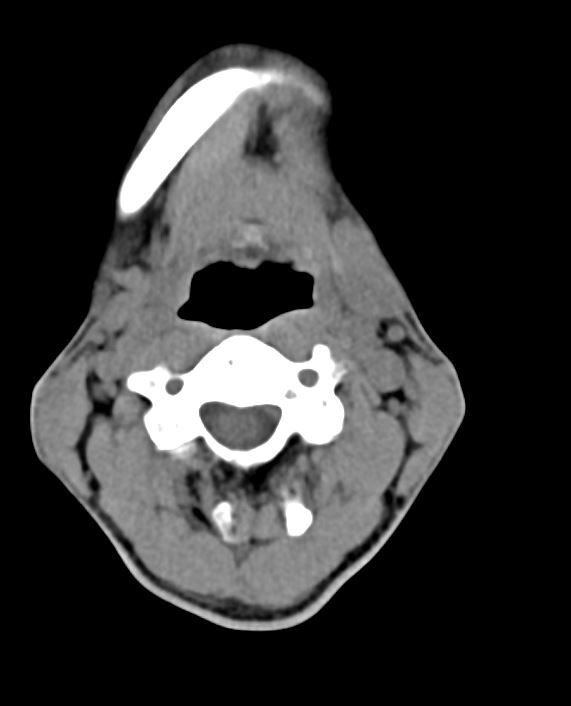

오랜기간 오른쪽 턱밑 타석증으로 인해 침샘이 많이 위축됐따고 합니다

2차병원 이비인후과 교수 말로는 타석증으로 인한 침샘염때문에 경동맥 쪽이 부을순 있는데

• 1번 째 사진